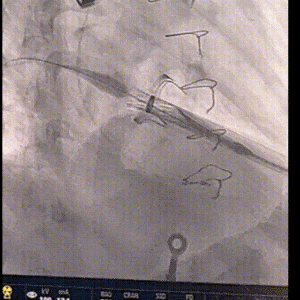

术中影像

加硬导丝盘置于左心房

160bpm起搏下初次释放瓣膜,瓣膜同轴性欠佳

160bpm起搏下部分回收瓣膜后,调整同轴性,第二次释放瓣膜

瓣膜位置良好,无张力脱钩

输送系统在心腔内完全闭合后撤出,配合收紧荷包

二尖瓣打开通畅,无瓣周漏

二尖瓣

最大流速:104cm/s

平均压差:术前21mmHg→ 术后2mmHg

无需进行球囊后扩张